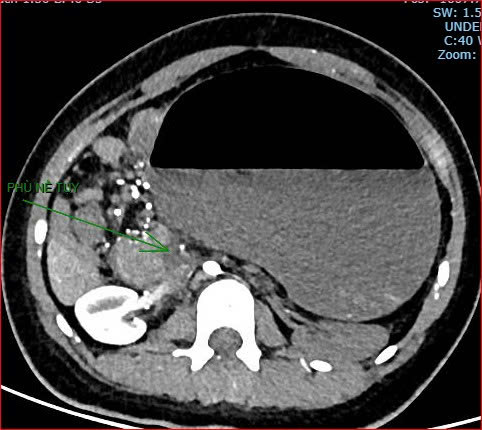

Khoảng 21 giờ 40, kết quả chụp CT cho thấy bệnh nhân rơi vào tình trạng cực kỳ nặng và hiếm gặp, bao gồm: xoắn dạ dày, nhồi máu thận trái, nhồi máu lách, viêm đầu tụy, viêm hỗng tràng, kèm dịch ổ bụng và tràn dịch màng phổi, trên nền bệnh nhân mắc hội chứng Down và tim bẩm sinh.

Hình ảnh chụp CT ổ bụng cho thấy dạ dày giãn lớn, xoắn bất thường; kèm tổn thương nhồi máu lách và viêm tụy trên nền ca bệnh hiếm, diễn biến đặc biệt nặng - Ảnh Bệnh viện cung cấp |